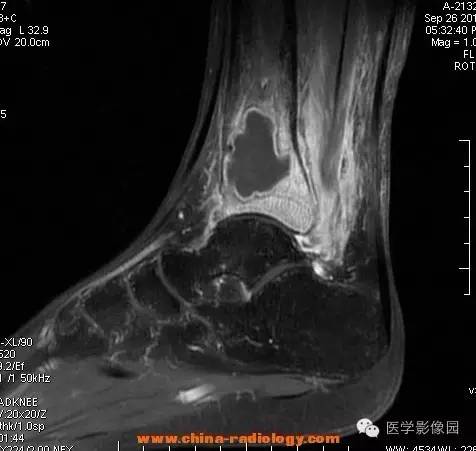

影像学表现:胫骨中下段干骺端不未规则形长T1长T2信号,T2WI见不完整环形稍低信号影,T2脂肪抑制低信号更明显,并见胫骨下段及踝关节后外侧软组织呈弥漫稍高信号,增强明显不均匀强化,增强见低信号环内有环形强化影。

影像学表现:表现为长骨干骺端有椭圆形密度减低区,边缘有清晰的骨质硬化,病变与邻近正常骨髓腔境界清楚。MRI上T1WI呈低信号,少数呈等信号,T2WI多为混杂高信号,增强扫描可见环状强化,强化的脓肿壁薄而均匀。